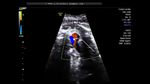

Color flow ultrasound image shows flow across the ventricular septal defect (VSD)

AVSD is also known as endocardial cushion defect or AV canal defect. It is caused by poor or faulty development of the endocardial cushion. These fetuses usually have other associated cardiac anomalies. The above images reveal large defects in the atrial and ventricular septae with a single large Atrio-ventricular valve replacing the mitral and tricuspid valves. In fact the the ASD is so large, that it appears like a single large atrium. Images courtesy of Dr. Latha Natrajan, Bangalore, India.